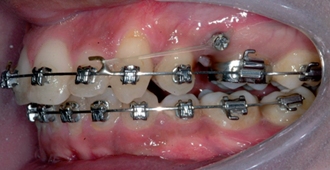

Дентальная галерея: ретинированный зуб клык и его лечение

Раздел: Компас решений